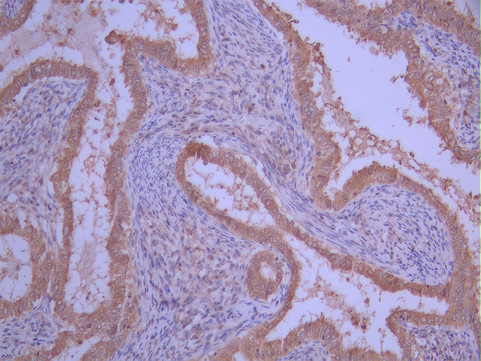

• IHC image of CSB-RA791753A0HU diluted at 1:100 and staining in paraffin-embedded human endometrial cancer performed on a Leica BondTM system. After dewaxing and hydration, antigen retrieval was mediated by high pressure in a citrate buffer (pH 6.0). Section was blocked with 10% normal goat serum 30min at RT. Then primary antibody (1% BSA) was incubated at 4°C overnight. The primary is detected by a Goat anti-rabbit polymer IgG labeled by HRP and visualized using 0.05% DAB.